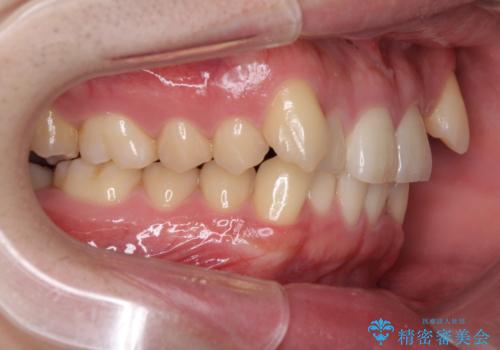

- 上顎の八重歯と前歯のデコボコを気にして来院された患者様です。

八重歯の移動量が多く、インビザライン単体での治療は困難と判断し、補助装置により八重歯移動後にインビザラインを用いることとしました。

上顎のみの抜歯矯正をインビザラインで行う場合、奥歯の前方移動がインビザラインでは苦手のため、奥歯の咬み合わせが不十分となることがあります。

今回の治療では終了時に奥歯は接触しているものの、接触の程度は物足りないものがある状態でした。今後保定期間に少しずつ奥歯の咬合を改善させていくことになります。